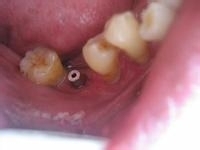

种植牙是一种专业针对牙齿缺失的解决办法,通过将人工牙根植入到牙槽骨,待人工牙根与牙槽骨紧密愈合后,再在牙根上植入牙冠。

3.固位好:不使用传统镶牙的卡环或牙套,人工牙根牙槽骨紧密结合,像真牙一样扎根在口腔里,具有很强的固位力与稳定性。